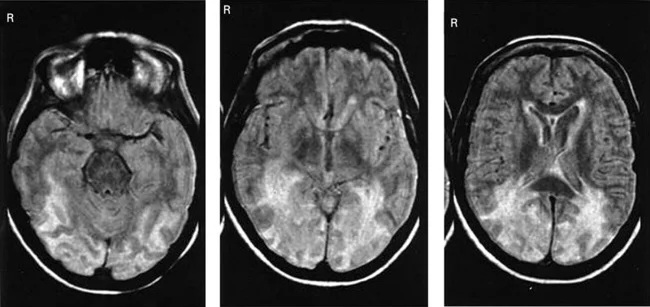

A typical symptom of this syndrome: the patient believes that someone close or loved to him has been replaced. This can also extend to pets or other significant objects. The disorder may more often be the result of neurodegenerative diseases or traumatic brain injury.